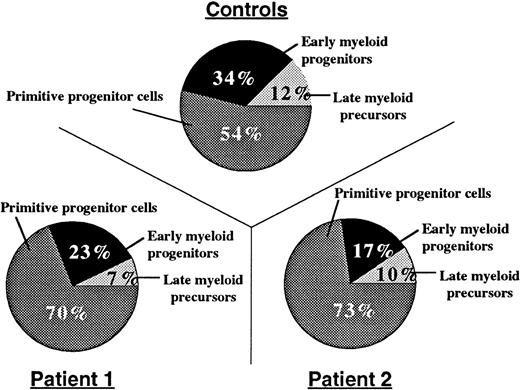

Bone marrow aspirates were hypercellular, and neutrophils were hypersegmented with nuclear lobes connected by thin filaments of chromatin (Figure 1). To determine the relative distribution of bone marrow myeloid compartments in patients with myelokathexis, we examined bone marrow CD34+ cells in colony-forming assays in soft agar in the presence of a cocktail of hematopoietic growth factors (SCF, Flt3 ligand, IL-3, G-CSF, and GM-CSF). On day 15, the resultant colonies were evaluated based on their morphology, density, and number of cells, and they were grouped into CFU-HPP (high proliferative potential primitive progenitor cells, more than 1000 cells/colony), early myeloid progenitors CFU-GM (more than 100 cells/colony), and late myeloid precursor CFU-GM clusters (<50 cells/colony). Colony-forming assays demonstrated that the proportion of CFU-HPP cells was increased, but the proportion of early and late CFU-GM cells was relatively decreased in patients with myelokathexis (Figure3). These data indicated a shift in the relative distribution of bone marrow myeloid compartments to more “primitive” cells in myelokathexis.

Compartments of bone marrow progenitor cells.

From healthy volunteers (n = 3) and 2 patients with myelokathexis, determined by colony-forming assays. 3 × 103 bone marrow-derived CD34+ cells, were plated on soft agar in the presence of hematopoietic growth factor mix, and the colony-forming units were assayed as described in Methods. Data represent the mean number of colonies from triplicate plates.

Compartments of bone marrow progenitor cells.

From healthy volunteers (n = 3) and 2 patients with myelokathexis, determined by colony-forming assays. 3 × 103 bone marrow-derived CD34+ cells, were plated on soft agar in the presence of hematopoietic growth factor mix, and the colony-forming units were assayed as described in Methods. Data represent the mean number of colonies from triplicate plates.

To delineate further the cell populations affected in myelokathexis, apoptosis studies were conducted with bone marrow-derived CD34+, CD33+/CD34−, and CD15+/CD34−/CD33− cell populations. These studies demonstrated that the rate of spontaneous apoptotic cell death was accelerated in bone marrow-derived myeloid progenitor cells from these patients (Figure 2). Analysis of bone marrow CD34+ cells by colony-forming assay demonstrated a substantial reduction in the bone marrow pool of myeloid-committed progenitors in patients with myelokathexis (Figure 3). Taken together, these data indicate that accelerated apoptosis of myeloid-committed progenitor cells contributes to the marked reduction in delivery of neutrophils from the bone marrow to the peripheral blood in myelokathexis.